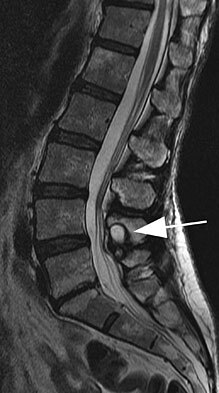

• What is the finding and what condition is this associated with?

• What level is most common?

• symptoms?

• treatment?

Facet Cyst (juxtalumbar facet cyst)

- L4-5 most common level (63%)

- Causes lateral recess stenosis, symptoms to the traversing nerve root.

- Highly associated with degenerative spondylolisthesis (82%).

- Presentation is indistinguishable from that of a herniated disk

- MRI: high signal intensity on T2-weighted image sequencing. It appears to be contiguous with the hypertrophied right facet joint, which appears to also have high signal intensity.

- Is it unstable radiographically? pre-operative flexion-extension films to evaluate for instability to include a potential fusion.

○ Yes:** laminectomy, cyst excision w/ instrumented fusion**

* Presence of instability potentiates recurrence of cyst

* Lower rate of recurrent back pain compared w/ laminectomy alone.